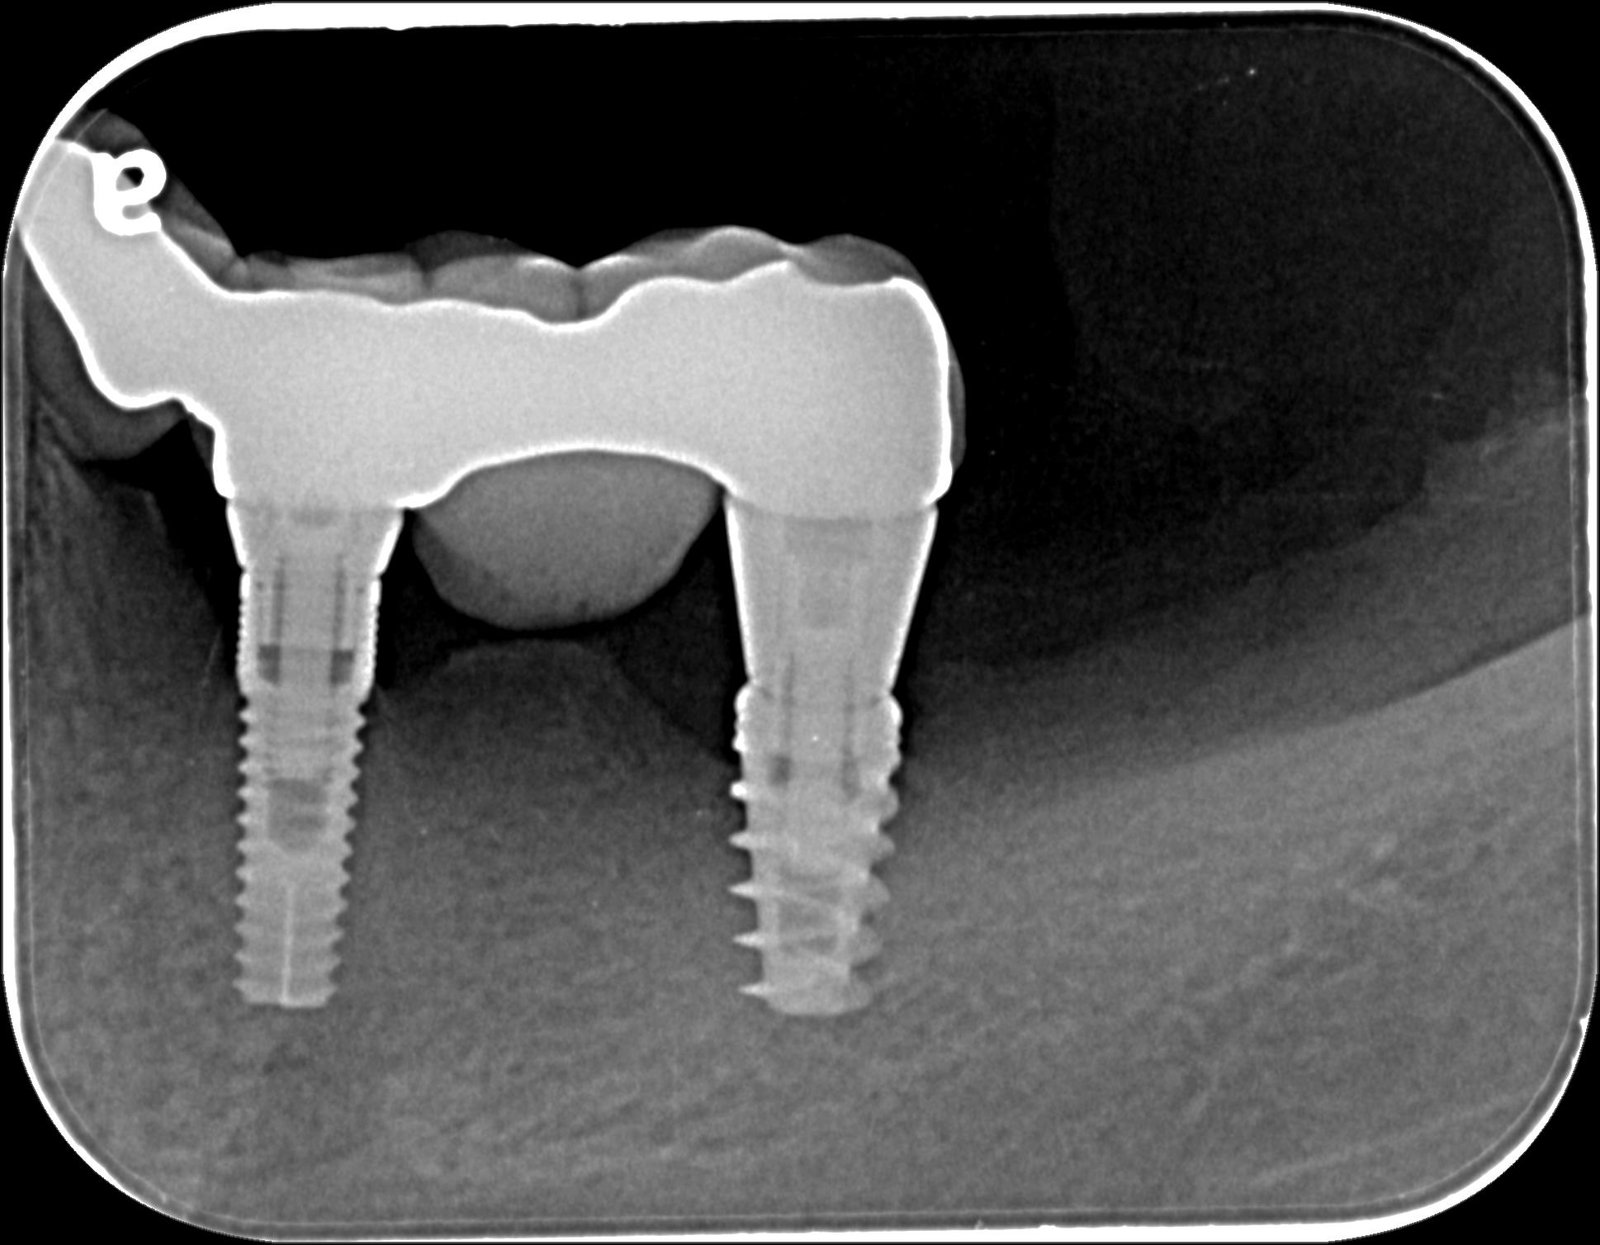

Paciente que acude a mi consulta con los implantes ubicados en el tercer cuadrante, los cuales son pilares de una prótesis fija sobre implantes. He decidido cambiar dicha prótesis pero [...]